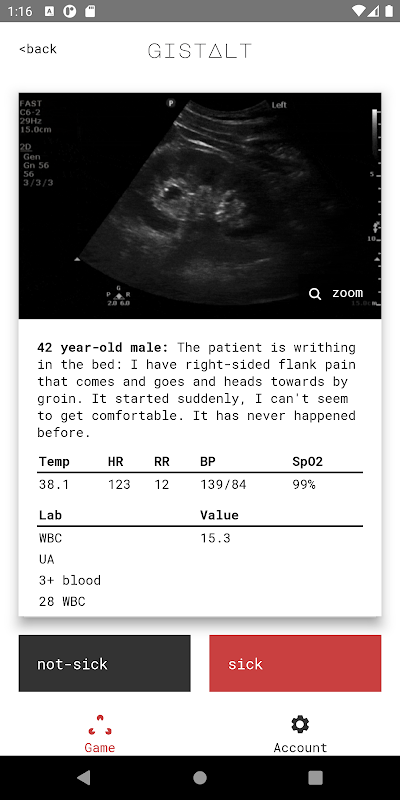

Matlamat anda bermain gistalt adalah untuk mengenal pasti pesakit mana yang sakit (memerlukan rawatan di hospital atau campur tangan segera untuk penstabilan) atau tidak sakit (keadaan yang dapat dirawat dengan selamat dengan tindak lanjut pesakit luar).

permainan gistalt mudah dan menyeronokkan. Anda akan memulakan dengan susunan persembahan pesakit termasuk tanda-tanda penting, hasil makmal dan pencitraan. Leret setiap kad ke kiri (untuk tidak sakit) atau ke kanan (untuk-sakit) untuk melihat soalan seterusnya. Di akhir timbunan, semak jawapan anda dan lihat skor anda. Skor gistalt anda secara khusus mengukur kemampuan anda untuk mengesan pesakit yang paling kritikal dan menjalankan rawatan yang akan memberi perbezaan.